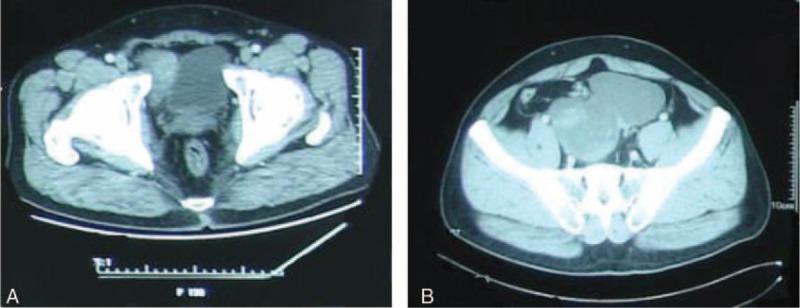

Solitary fibrous tumor of the pelvic is an uncommon neoplasm with nonspecific symptoms. Reports of malignant transformation are especially rare. We report a case of solitary fibrous tumor in pelvic. A unique feature of our case compared with previously reported is that this patient relapsed with malignant transformation and had significant response to radiotherapy. The patient was initially treated with surgery, followed by postoperative dimensional conformal intensity modulated radiation therapy (dynamic MLC VRIAN 23EX Linac, inversely optimized by the Eclipse system) to provide a radical cure for residual tumor.In this case, there were no signs of recurrence after six and a half years of further follow-up, indicating that postoperation radiotherapy may be an effective treatment for SFT with malignant transformation in pelvic.

盆腔孤立性纤维瘤是一种具有非特异性症状的罕见肿瘤。恶性转化的报道尤为罕见。我们报告一例盆腔孤立性纤维瘤病例。与先前报道相比,我们病例的一个独特特征是该患者出现恶性转化复发且对放疗有显著反应。患者最初接受手术治疗,随后进行术后三维适形调强放射治疗(使用动态多叶准直器的瓦里安23EX直线加速器,由Eclipse系统进行逆向优化)以根治残留肿瘤。在该病例中,经过六年半的进一步随访没有复发迹象,表明术后放疗可能是盆腔恶性转化孤立性纤维瘤的一种有效治疗方法。